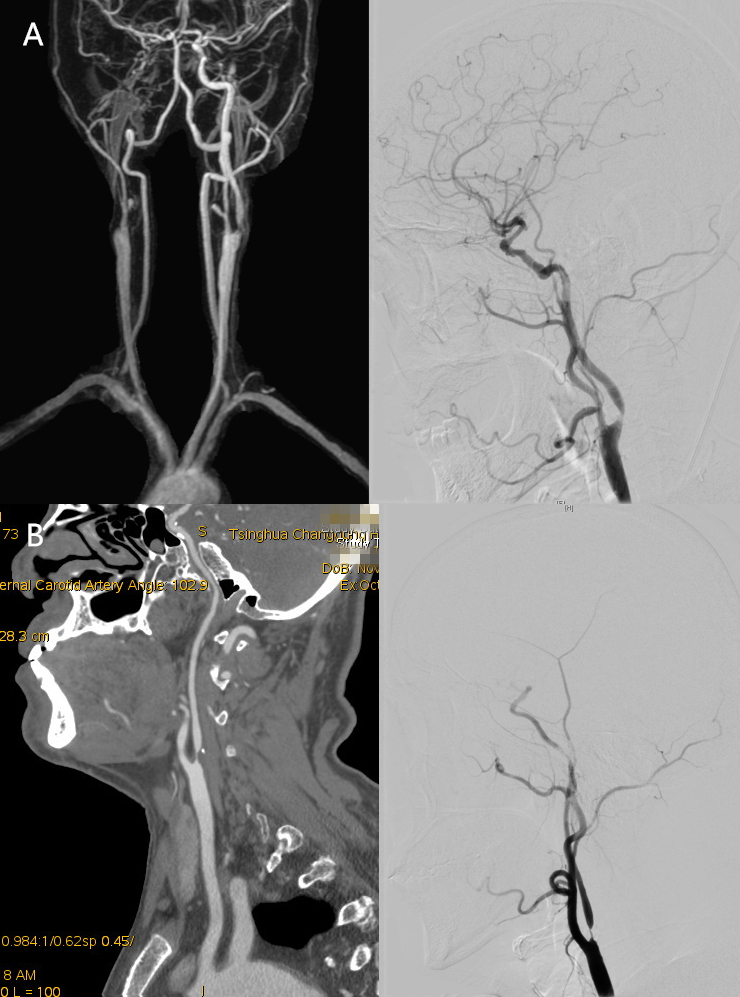

1例患者右侧颈内动脉闭塞、左侧颈内动脉重度狭窄,采用转流管转流(A);1例患者左侧颈内动脉重度狭窄,颅内血流代偿可,采用eCEA术

CEA术式包括传统颈动脉内膜剥脱(cCEA)、内膜剥脱+补片成型(pCEA)、外翻式颈动脉内膜剥脱(eCEA)。pCEA应用补片改善直接缝合造成的血管狭窄。eCEA手术时间短,血流阻断时间短。颅内对侧血流代偿能力差的患者,难以耐受血流阻断,目前多采用转流管临时桥接血流,在剥脱斑块的时候也能保证颅内血液供应。有经验的专科医师会根据病变特点、颅内血流代偿情况等术前评估结果,选择合适的CEA术式,完成颈动脉狭窄的精准治疗。